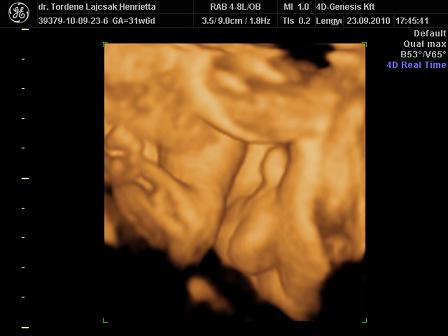

tegnap voltunk Uh-n. minden rendben van vele, egyre nagyobb. :)

méreteink:

BPD: 79,7 mm

HC: 292,5 mm

AC: 268,5 mm

FL: 57,8 mm (ezt nem tudta pontosan lemérni, mert érdekesen pózolt )

súly: 1700 g. (netes kalkulátor alapján 1750)

rakok róla néhány képet. :oops: és már 32 hetesek vagyunk...lassan finish.. :)